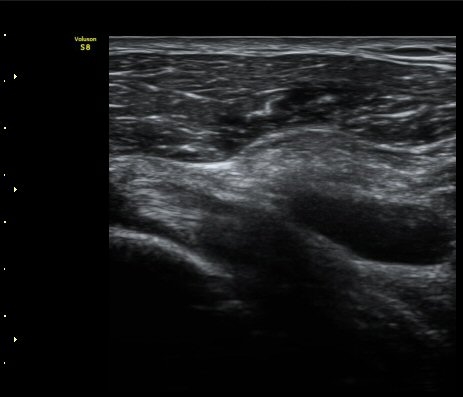

¿À±¸µ¹±â Á¾´Ü¸é°Ë»ç½Ã ¿À±¸ µ¹±â ³»Ãø, ¿À±¸µ¹±â ¾Æ·¡¿¡ ¼ö¾×Àú·ù°¡ °üÂûµÈ´Ù(±×¸² 5, 6).